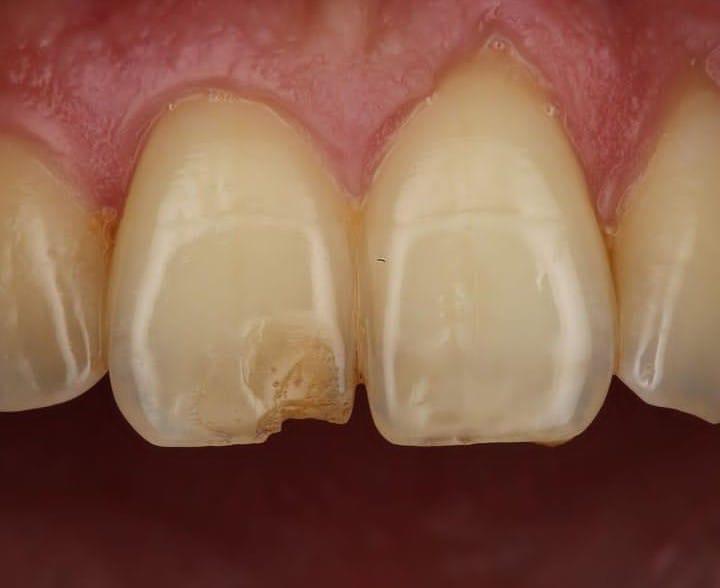

Es un procedimiento quirúrgico dental que consiste en la remoción de una parte del tejido gingival (encía). Se realiza principalmente por dos razones:

1. Estética: Para mejorar la apariencia de la sonrisa, por ejemplo, en casos de “sonrisa gingival” donde se muestra mucha encía al sonreír.

2. Terapéutica: Para tratar enfermedades periodontales, eliminando tejido afectado por inflamación crónica, permitiendo una mejor limpieza de las bolsas periodontales.